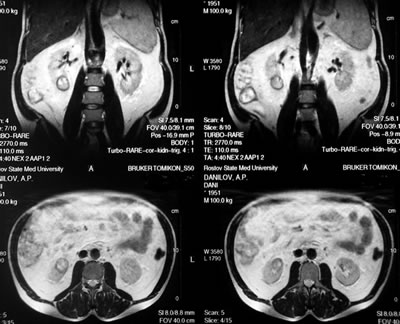

Магнитно-резонансная

томография (МРТ)

правая почка: в нижнем сегменте

образование диаметром 32 мм, с неоднородной структурой

и участками кровоизлияний; в верхнем сегменте – две

кисты 13 и 19 мм